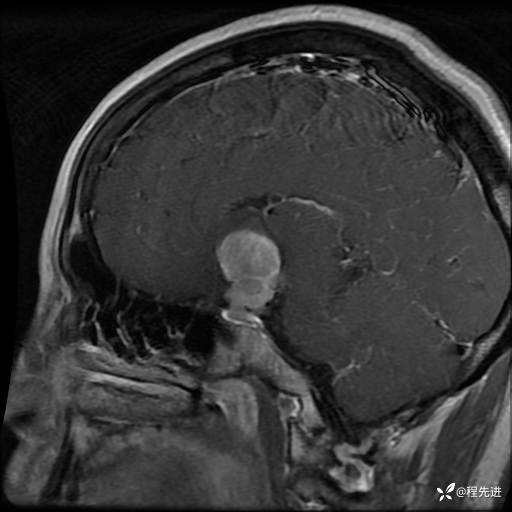

MRI平扫+增强:

T1+C: